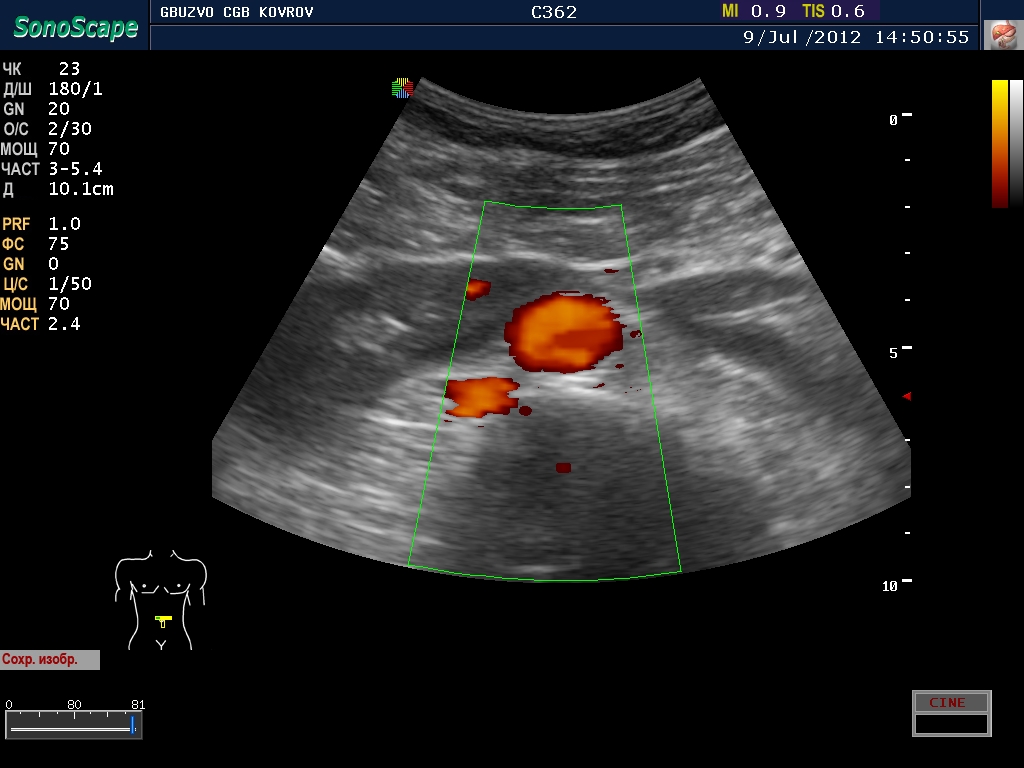

Добавлю с разрешения коллег, свое наблюдение...

Вот нифига себе! Это ребёнок?

:D Почему ребенок, дяденька 45 лет! а что вас смутило?

Расположение. Сгрудились у аорты...

расположение аномальное - подковообразная почка 8-) четко виден перешеек!

В своё время не разъехались. А жить то ему это мешает? Наверное нет.

живет..хлеб жует...нет не мешает.